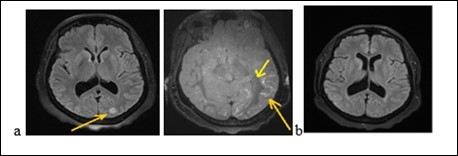

A 31-year-old pregnant woman was admitted to hospital because of headaches, vomiting and rotational dizziness on December 29, 2017. A series of headache followed by vomiting and dizziness began at 33 weeks of pregnancy (a month before her admission). We noticed that the blood pressure reached 150 / 90mmHg. She was treated with oral nicardipine for one month. The delivery took place without postpartum complications. She had been treated with bromocriptine for breast congestion. Three days after delivery, she had thunderclap posterior headache, nausea chills with asthenia without fever, polyuria and polydipsia. The manifestation of the headache was 9.5 / 10 on the Visual analogical Scale. In her medical history, she underwent a surgery of an ovarian cyst and a left temporal arachnoid cyst in 2007. She is an active smoker at 15 boxes-years. The neurological and other physical examinations were normal. The routine biological, metabolic, infectious and immunological check-up was normal. The MRI had displayed a subarachnoid hemorrhage associated with hypersignals on Flair sequences of bilateral hemispherical cortex, on the central gray nuclei and the cerebellar hemispheres. The Angiography had not shown any stenosis. The MRI (Figure 3) had displayed on diffusion sequences, two punctiform infarction of right putamen and caudate nuclei. The apparent diffusion coefficient was high for the other bi-frontal lesions. All these findings led us to conlude with RPE syndrome complicated by subarachnoid hemorrhage and cerebral ischemia. The patient had been treated with decreasing dose of nimodipine for three months. At 6 weeks of progress, the neurological examination was normal. The Brain MRI (Figure 3b) displayed a complete decrease of the flair hyper signals from the basal ganglia and the cortex. The outcome was good.

Figure 3.The brain MRI with flair sequences showing bi-temporal and frontal hyper signals (a) and a complete decrease of lesions after treatment (b).

The brain MRI with flair sequences showing bi-temporal and frontal hyper signals (a) and a complete decrease of lesions after treatment (b).